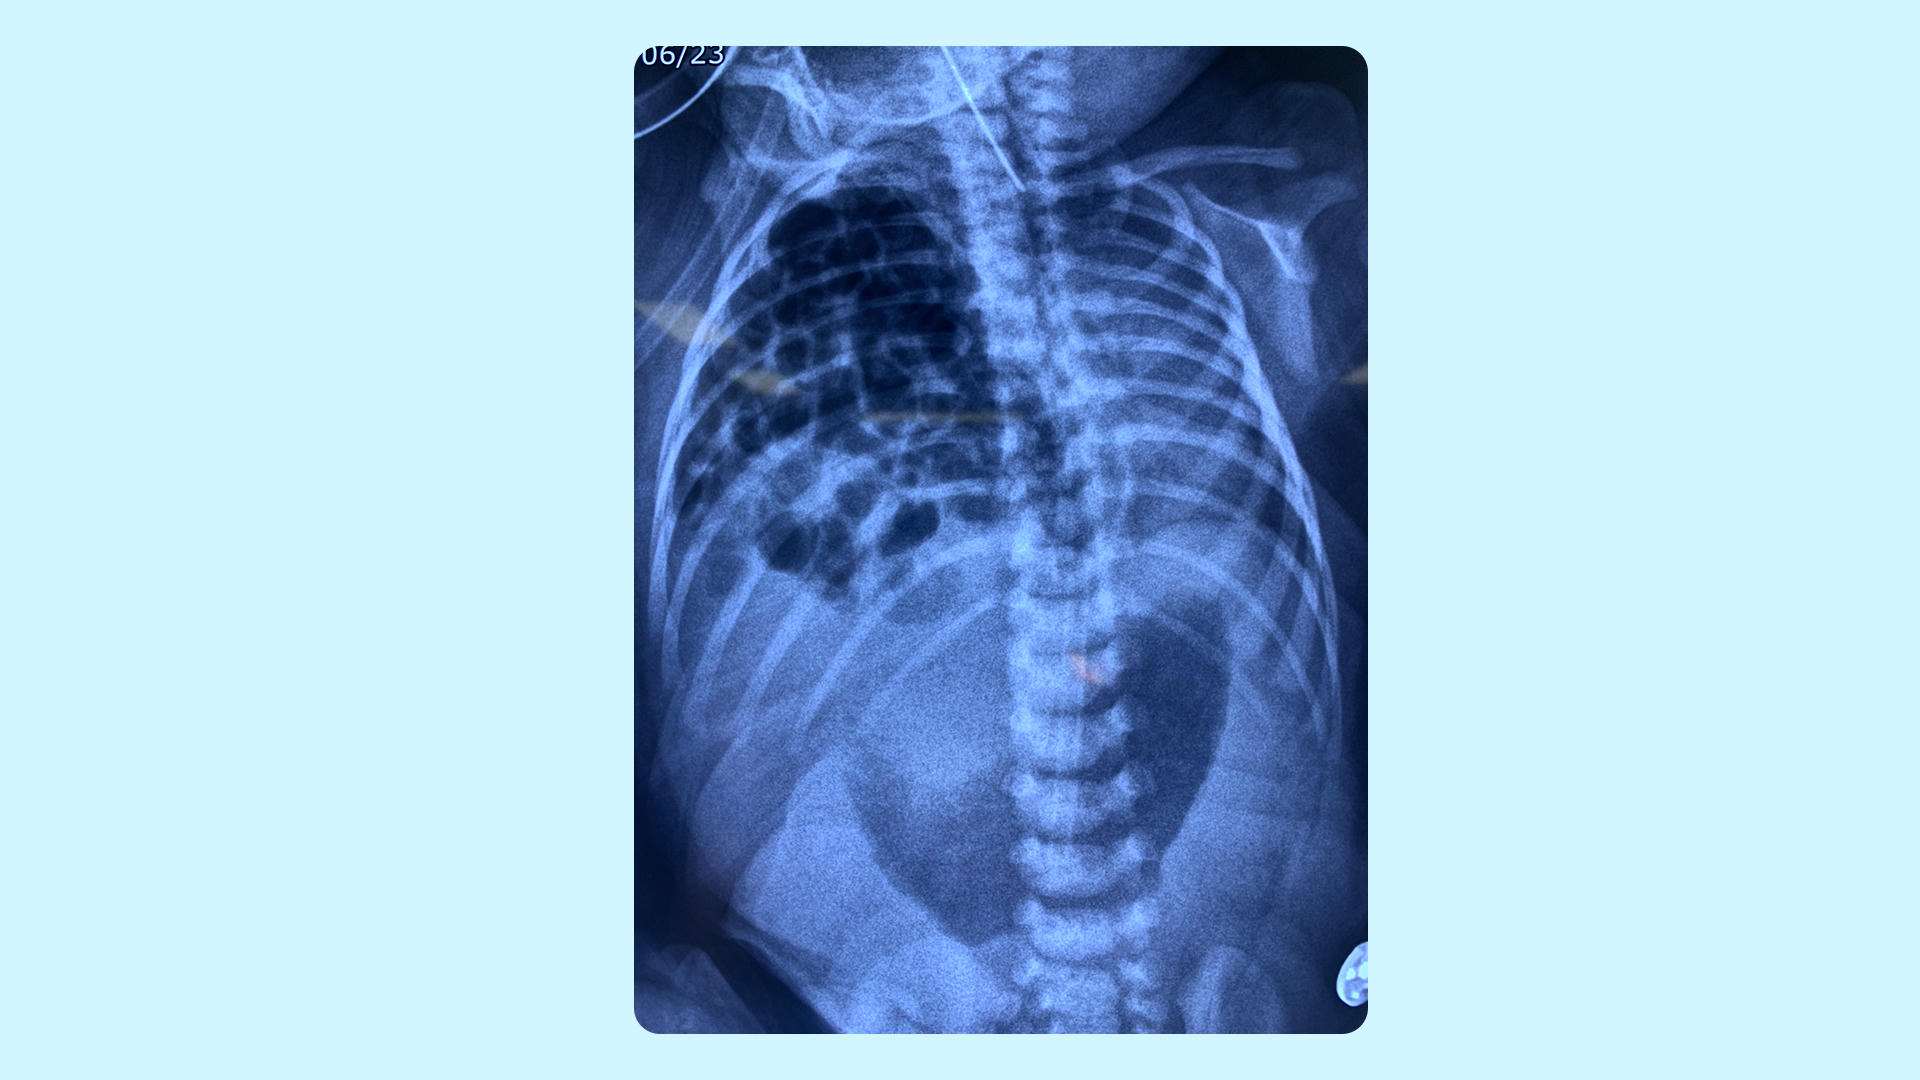

Bé An được chăm sóc tích cực ngay sau sinh. Ảnh: Hạ Vũ |

Ngay sau sinh, bé An rơi vào suy hô hấp do cao áp phổi (tăng áp lực trong tuần hoàn phổi), được đặt nội khí quản và phụ thuộc vào máy thở 24/24. Lúc này, nếu phẫu thuật ngay cho bé thì tỷ lệ tử vong rất cao do tình trạng hô hấp chưa ổn định. Ngược lại, nếu để quá lâu, cơ hội sống sẽ mong manh do cao áp phổi kéo dài, nhiễm trùng cơ hội sau đó.

“Giải pháp duy nhất để cứu sống bé là chăm sóc tích cực tại phòng NICU bằng máy thở, thuốc vận mạch, thuốc dãn mạch phổi, dinh dưỡng tĩnh mạch… nhằm ổn định huyết động càng sớm càng tốt, tạo tiền đề cho ca mổ diễn ra an toàn”, TS.BS Đỗ Hữu Thiều Chương, Phó giám đốc Trung tâm Sơ sinh BVĐK Tâm Anh nhấn mạnh.

Khi bé An được 4 ngày tuổi, ca phẫu thuật thoát vị hoành được tiến hành. BS.CKII Nguyễn Đỗ Trọng, chuyên khoa Ngoại Tim mạch - Ngoại Nhi BVĐK Tâm Anh cùng ekip đưa các cơ quan bị lạc chỗ về đúng vị trí rồi khâu phục hồi cơ hoành. Sau 1 giờ, ca mổ kết thúc.

Ba ngày sau, bé An cai máy thở, tập bú sữa và có thể đi ngoài, áp lực động mạch phổi được kiểm soát tốt. “Sự hồi phục ngoạn mục của bé An chỉ vài ngày sau mổ đã khẳng định tầm quan trọng của “kiềng ba chân” Sản Phụ khoa - Sơ sinh - Ngoại Nhi trong việc cứu sống những em bé bị dị tật bẩm sinh phức tạp”, BS.CKII Nguyễn Đỗ Trọng chia sẻ.